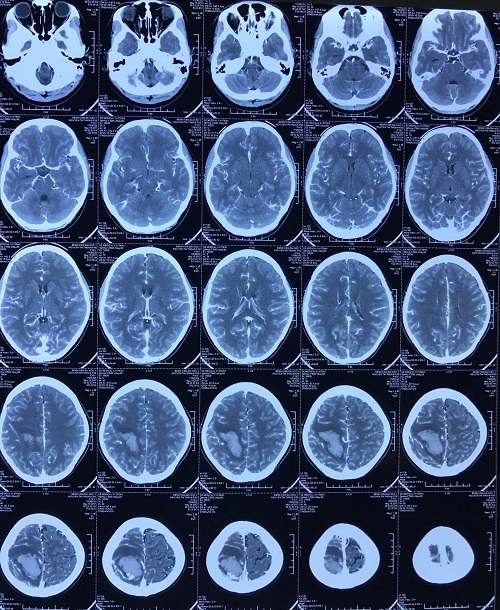

Kết quả chụp MSCT phát hiện khối dị dạng động tĩnh mạch vùng vận động gây liệt nửa người. Bệnh nhân được chỉ định mổ cấp cứu: lấy máu tụ trong não, lấy khối dị dạng mạch. Sau mổ bệnh nhân tỉnh, tự co chân tay được, còn yếu nhẹ nửa người trái. Sau 5 ngày bệnh nhân đã ra viện.

| Hình ảnh dị dạng mạch não trước và sau phẫu thuật. |